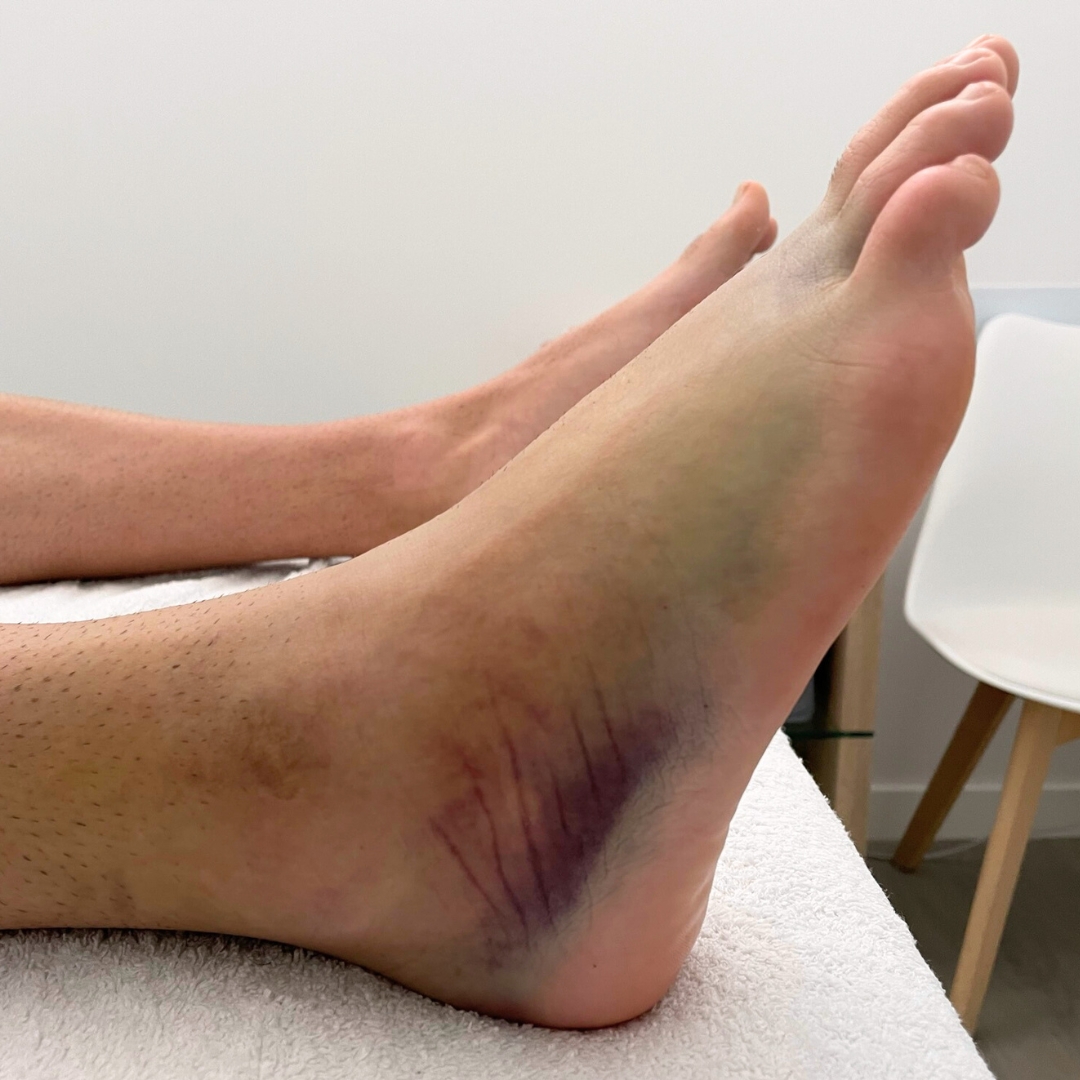

Esguince de Tobillo